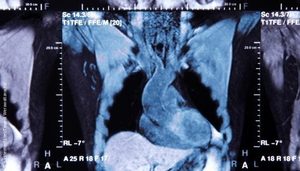

Cardiovascular magnetic resonance (CMR) is the gold standard for diagnosing many cardiovascular diseases. It is used to measure the structure and function of the heart, and to assess scarring on the heart muscle after a heart attack.

Image: panthermedia.net / Tawesit Werawattanachai